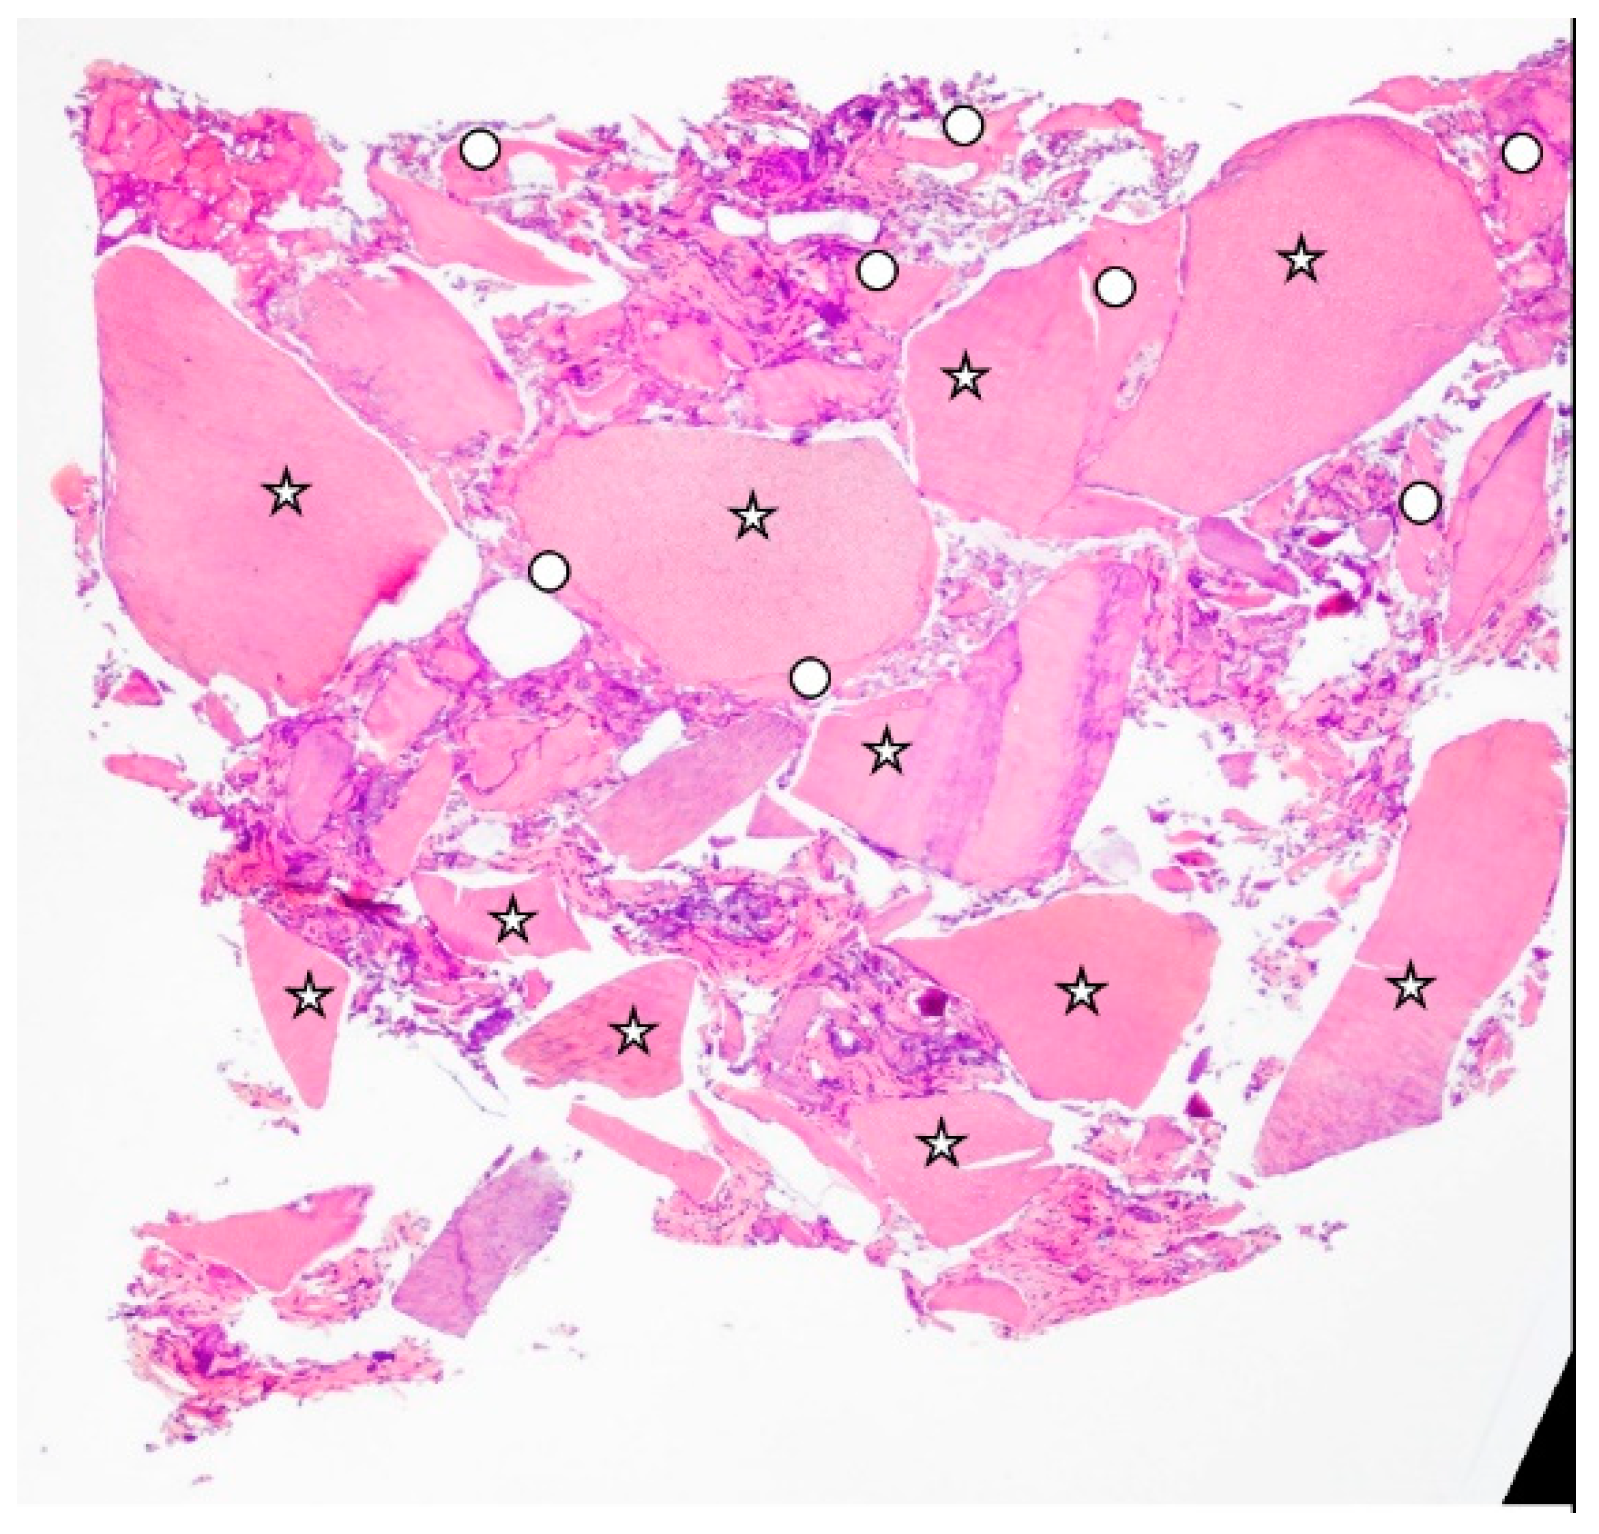

- Bone volume % (BV%), which represented the percentage of mineralized tissue with the exclusion of medullary tissues.

- Tooth Transformer graft % (TT%), which represented the percentage of the volume occupied by the remaining graft, namely dentin.

- Vital bone % (VB%), which represented the percentage of vital bone, excluding medullary tissues.

| Bone Volume % | 45.69 ± 2.31 | 37.34 ± 6.33 |

| Residual Graft % (TT%) | 7.26 ± 2.28 | 27.54 ± 15.42 |

| Vital Bone % | 38.42 ± 4.58 | 9.75 ± 11.81 |